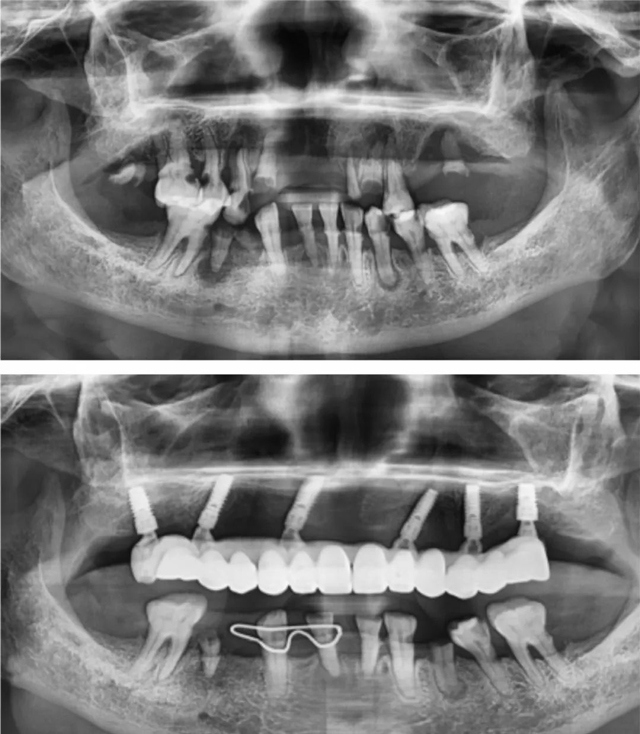

患者術前術后全景片

曾經(jīng),一位八十多歲的阿姨,其上牙全是爛牙根,由于就醫(yī)不便,牙齒問題一直被擱置。韓沛接診后發(fā)現(xiàn),阿姨骨量極差,骨頭很薄,進行半口種植手術存在一定難度。面對復雜的牙齒狀況和聽不懂的專業(yè)術語,阿姨和家屬有些慌張與迷茫。

韓沛沒有絲毫的不耐煩,與阿姨及其家屬進行了多輪耐心細致的溝通,將每一項風險都清晰明確地告知,用通俗易懂的方式講解有關半口種植的情況,還結(jié)合阿姨的自身情況給出了科學合理的應對方案。阿姨和家屬被韓沛的專業(yè)與負責深深打動,對于手術也不再緊張,最終決定接受手術。

在患者和家屬的高度信任下,手術得以順利開展。術后,阿姨十分滿意,生活質(zhì)量得到了極大提升,她逢人便夸這位韓醫(yī)生醫(yī)術高超、耐心又有親和力。